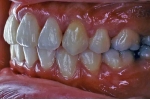

初診時